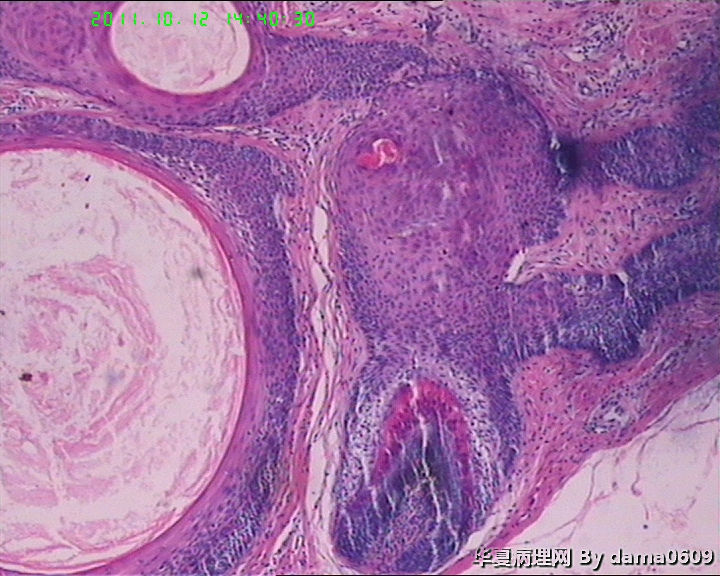

女,42岁,右眼外上方皮下肿物4年。

送检:椭圆形肿物,v:0.5x0.5x0.4cm,实性,灰白色,质软。

• 眼角旁皮下肿物,不会了啊!!图1

图1

毛发腺瘤

看起来,是否要考虑毛发上皮瘤?

镜下大部分都是毛囊结构,要考虑毛囊痣。